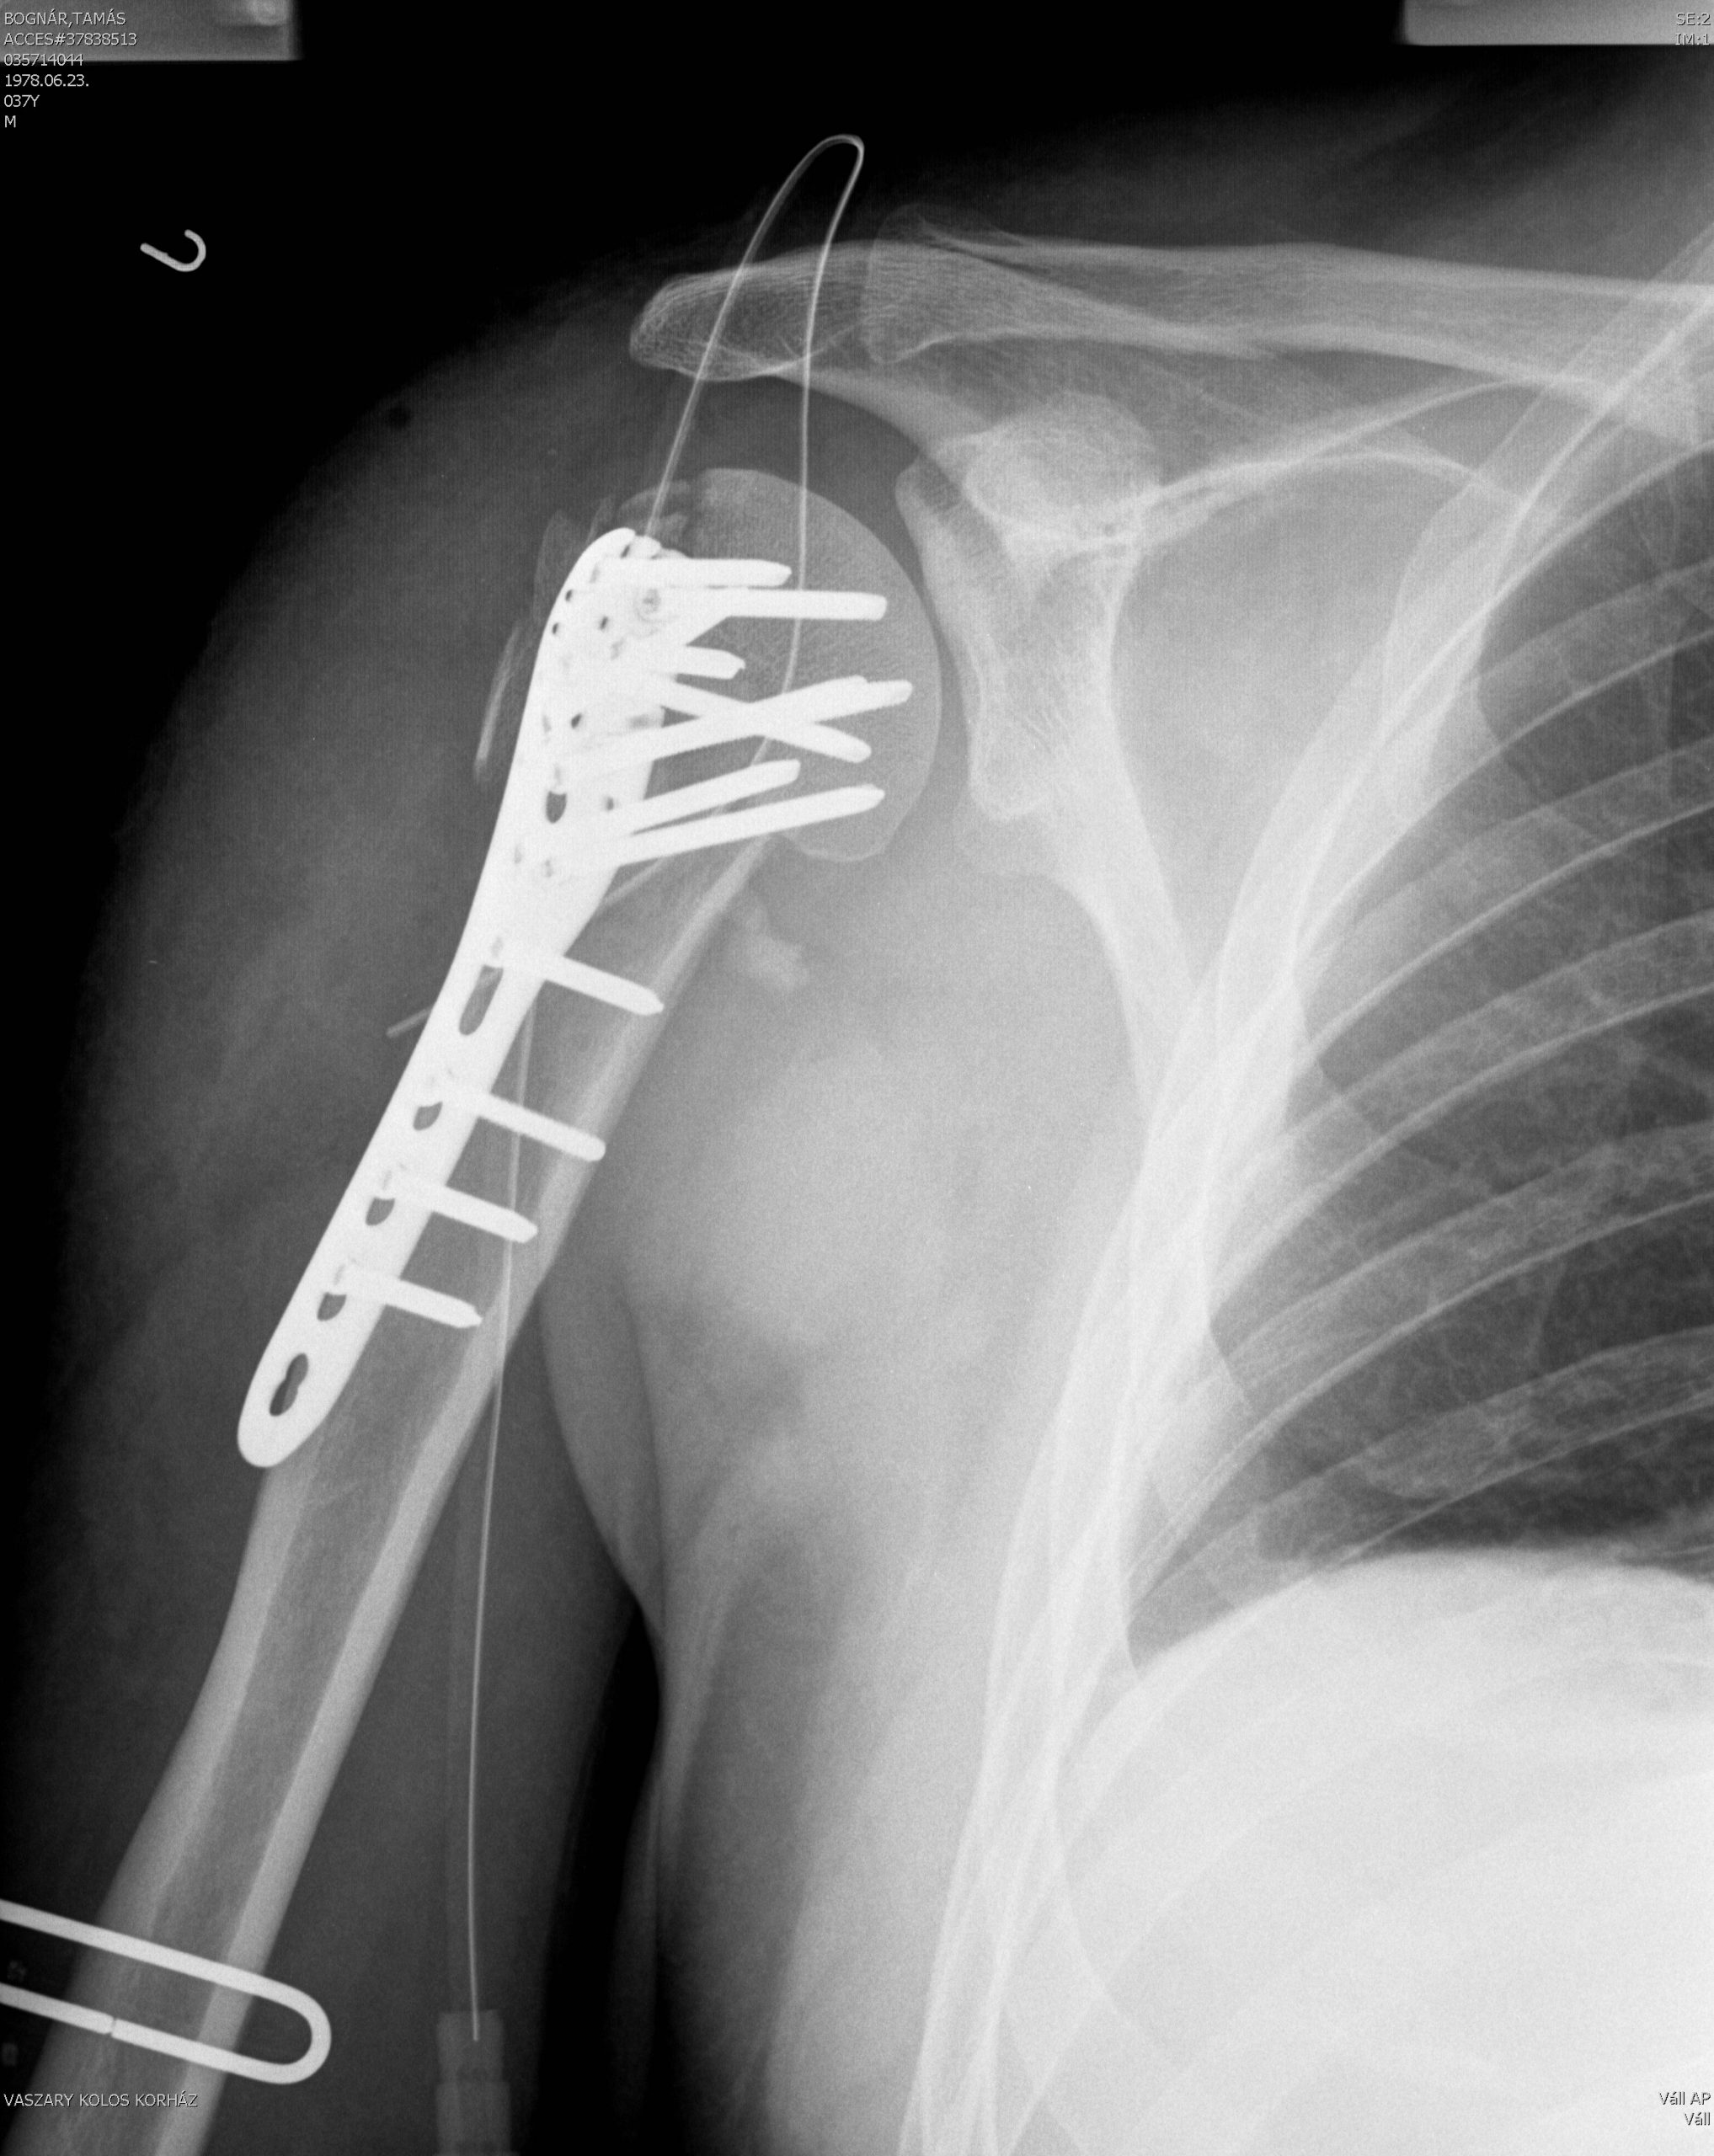

És honnan tudod hogy igazán megéri egy ruha vagy sisak az árát azon felül, hogy kényelmes, szellőzik, jól néz ki vagy könnyű? Ha esel benne egy nagyot… Sajnos maximálisan le lett tesztelve az iXS szett. A sors fintora, hogy a térdvédő nem volt rajtam mert egy „sima” bringateszt alatt történt, ahol nem volt sem tempó sem extrém helyzet. Mondjuk a térdemet szerencsére nem vertem be. A vállam az eltört, lefejeltem egy követ, és odavertem a jobb oldalamat. Mikor kijöttem a kórházból, megnéztem a cuccaimat. A sisakon egy horpadás jelezte, hogy köszöni elvégezte a dolgát, megvédte az életem és mehet fel a polcra a többi régi/törött fejvédőm mellé.